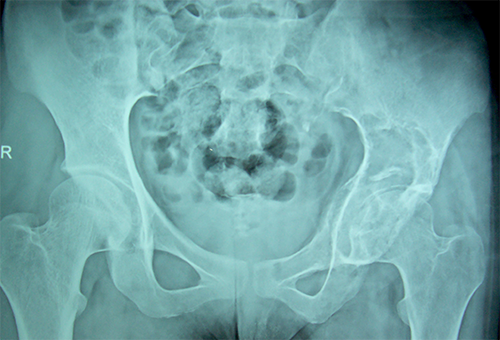

Case:4 GCT Acetabulum

Orthopedic Oncology Doctor|Spine Surgeon Best In Rajasthan

Pre-Op

Best spine surgeon in ahmedabad|Best Trauma Surgeon

Post-Op Scraooing + B.G